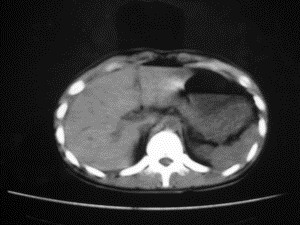

患者女,20岁,被车撞伤3小时,pe:全腹肌紧张,压痛反跳痛,以右上腹为著,肠鸣音减弱。有手术结果。![]() ![]() ![]() ![]() ![]() ![]() ![]() ![]() ![]() ![]() ![]() ![]() ![]() ![]() ![]() ![]() ![]() ![]() ![]() ![]() ![]() jiajie发言: ![]() 考虑空腔脏器穿孔。 dyqct发言:考虑:1、肝左叶外侧段断裂伤伴少量腹血。2、空腔脏器穿孔。 fangzheng发言:仅见腹腔内游离气体,提示空腔脏器穿孔。 guoke发言:胃内密度增高,肠腔内充满气体,考虑肠腔破裂出血 mmg94发言:胃后壁见一增厚软组织密度影,肝左叶前见游离气体影,左腹腔内局部肠管壁、系膜增厚。并见类圆形软组织。以上征象提示消化道管腔破裂,小肠、肠系膜挫裂伤,腹腔血肿形成。 拾荒者发言:肝实质密度不均匀,胃内见不均匀高密度影。考虑:肝挫裂伤,胃内应激性溃疡出血。 守望可可西里发言: 以下是引用jiajie在2006-6-20 15:49:00的发言:[br] [br][br]考虑空腔脏器穿孔。jiajie老师,我鼓起了很大的勇气才决定给您唱个反调儿,如果我错了,请您一定给我指出来,谢谢您了。我反复看了解剖图谱,觉得您所说的“考虑空腔脏器穿孔”上图所用箭头标明的不是游离气体。请您看以下几幅图片: ![]() ![]() ![]() ![]() ![]() ![]() ![]() ![]() 再请您看向医生老师发表的解剖图谱3幅 ![]() ![]() ![]() 这以下几幅图,我认为是肝包膜下积血。不过,说实在话,我没有发现有明显的肝挫裂伤。不对的地方请您一定指出来,再次感谢您了,jiajie 老师! ![]() ![]() ![]() ![]() 这下面几幅图片,我认为有明显的左中上腹部小肠损伤。 ![]() ![]() ![]() ![]() ![]() ![]() ![]() ![]() jiajie 老师,估计我说的是错误的,但我实在闹不明白,请您一定不要笑话我,并指出我的错误,以便于我减少工作中的失误。再次感谢您了,jiajie 老师! 至于胃内的不均匀高密度,我认为拾荒者战友说的有道理,胃内应激性溃疡出血和胃内容物混合所致。 手术结果:左肝叶(iv段)前缘长约8cm挫裂伤口,舌叶根部下< |